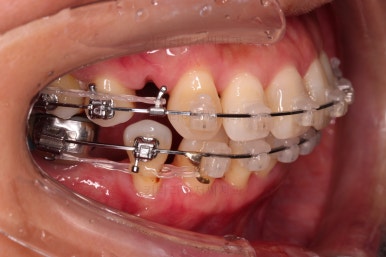

동래임플란트교정 초진 시 입안의 모습입니다.

치열이 전반적으로 삐뚤어져 있는 양상이고요.

아랫니가 윗니보다 더 많이 삐뚤어 있는데요.

장치를 부착했습니다.

이번 환자분이 선택한 장치는 데이몬 클리어라고 하는 현존하는 자가결찰 세라믹 장치 중에 가장 심미적인 장치입니다.

사실상 멀리서 보면 철사를 제외하고는 거의 눈에 띄지 않는 모습인데요.

단점은 부피가 다른 장치들보다 약간은 더 크기 때문에 입이 약간 더 나와보일 수 있다는 점이죠.